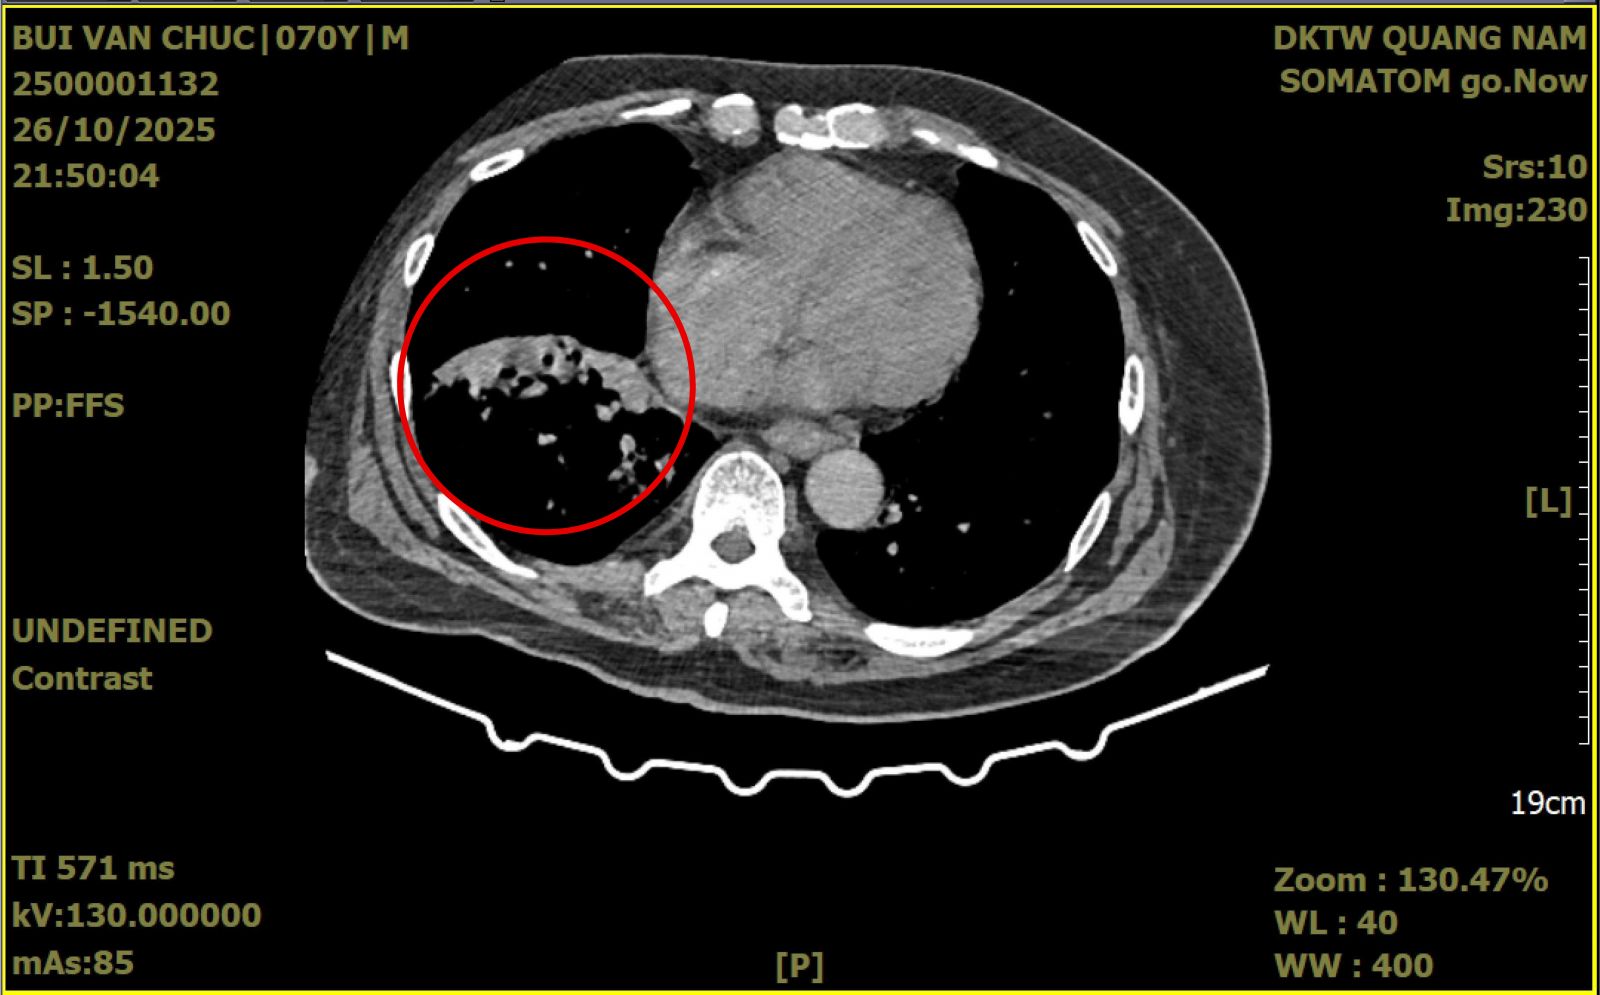

Hình ảnh chụp CT trước mổ của người bệnh Chúc bị dãn phế quản thùy dưới phổi phải.

Kết quả thăm khám lâm sàng và nội soi khí phế quản cho thấy máu chảy từ phế quản thùy dưới phổi phải. Hình ảnh chụp cắt lớp vi tính xác định có tổn thương giãn phế quản khu trú tại thùy dưới phổi phải.